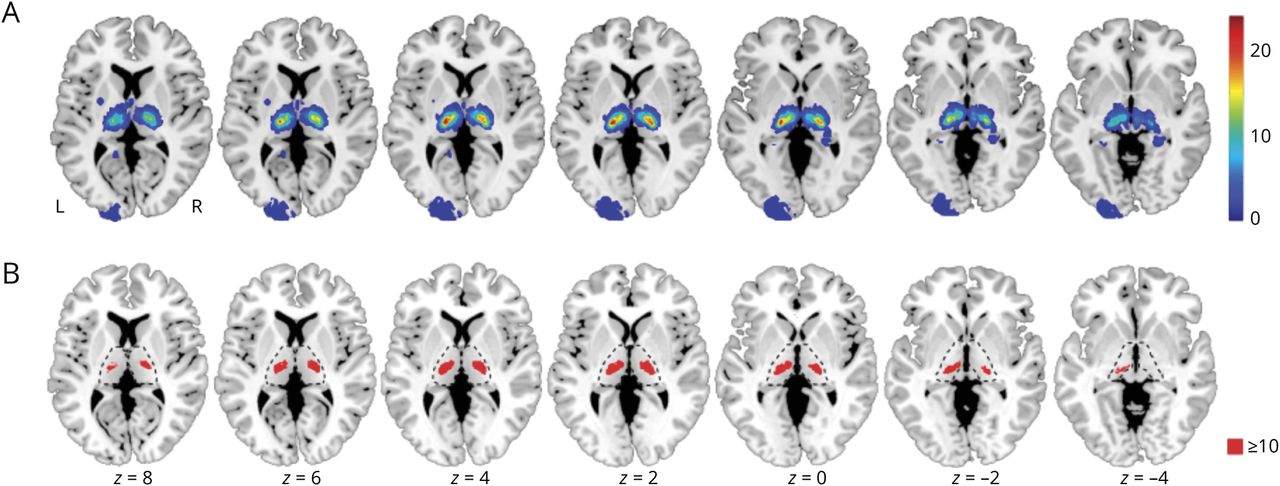

与无语言障碍的患者相比,有语言障碍的患者与左侧额上回和中回(Brodmann区[BAs] 9、10、46,对应于前额叶前部和背外侧皮层)和左侧顶叶下(BA 39、40)的病变依赖网络连通性(LNC, p(FWE)在聚类水平上< 0.05)显著升高。此外,这些患者的左脑岛和左额下回(BA 45,47)、左颞下回和中颞回(BA 20,21,37)以及左背中核和前丘脑核(BA 20,21,37)有较高的LNC。图4一而且表2).所有显著的聚类均位于左半球。相比之下,与无构音障碍的病变依赖网络患者相比,构音障碍与右上上回和中额回(ba9,10,46) LNC相关。此外,它与双侧扣带皮层(BA 24,32)、右侧补充运动皮层(BA 6)和左侧小脑(BA 6)的高LNC有关。图4 b而且表2).

与没有相应症状的患者相比,病变网络-症状映射分析确定了较高规范的病变依赖网络连通性与(A)语言障碍、(B)构音障碍和(C)右侧感觉或(D)运动缺陷相关的区域。在网络功能障碍导致损伤的假设下,这些网络中的功能相互作用有助于语言、发音、感觉和运动的生成和感知。对于所有分析,统计推断基于随机排列检验阈值,在聚类水平上p(FWE) < 0.05。突出显示的体素在组之间有显著差异。与其他丘脑卒中症状患者相比,语言障碍患者的左半球下额叶和颞叶语言网络和区域一般网络(岛叶、前额叶和顶叶皮层)显示出明显更大的病变依赖网络连通性。坐标:MNI空间。FWE =家庭错误;蒙特利尔神经学研究所。

与语言和构音障碍相比,左右感觉和运动缺陷出现了不同的FC模式。为了更好地进行比较,下面我们将重点关注右侧赤字(左侧赤字,见图1,表2,links.lww.com/WNL/C447).与无右侧感觉缺陷的患者相比,双侧前额叶皮层(额中上回和眶额皮层)、中央后/上顶叶皮层(左>右)、左侧中央前皮层以及左侧腹侧丘脑核和枕部的LNC更高。此外,这些患者表现出较高的双侧小脑(右>左)、颞叶和中颞叶连通性(图4 c和表2)。与没有右侧运动缺陷的患者相比,发现了非常相似的模式。它包括较高的LNC与双侧额中回和上回,左侧中央前和中央后皮层,左侧腹侧丘脑核和枕状核。此外,双侧基底神经节(壳核和苍白球)和右侧小脑(图4 d表2)。

对于语言障碍,LNSM显示较高的LNC被识别为左半球额颞叶语言网络(左额下回,下回和中颞回),涉及语音及其含义的表示和处理。36此外,高LNC的区域可以被总结为域-一般网络(双侧前额叶腹侧和背外侧,中间和前扣带,岛盖皮层和顶叶皮层)也有助于语言障碍。语言能力需要语言网络和参与高阶认知过程的双边域通网络之间的联合处理。31,32反映本研究中确定的所有区域,区域一般网络可以进一步细分为由背外侧前额叶、中扣带皮层、楔前叶和下顶叶组成的额顶叶网络和包括前前额叶皮层、前岛叶、额盖和前扣带皮层的扣带-盖叶网络。37这两个网络分别为认知控制的启动和维持提供了灵活的资源,从而涉及有效的认知加工。38尽管关于这种执行控制操作如何影响语言处理的争论仍在继续,但从分布式语言网络中的多个集中选择与任务或目标相关的网络组件(例如,访问一个单词的含义或产生一个语音序列)可以被认为是由域通用网络介导的一种机制。31,39,40与局灶性病变引起的功能障碍的概念相一致,这些网络中的中断处理很可能有助于丘脑卒中后观察到的语言障碍。特别是丘脑失语症的特征是言语不连贯和不连贯41可能被认为是与语言有关的结构未受损的皮层区域之间处理控制较少的结果。在我们无法为潜在的神经元过程提供实验证据的限制下,在接下来的文章中,我们综合了已确定的丘脑皮层网络如何协同贡献语言的发现。